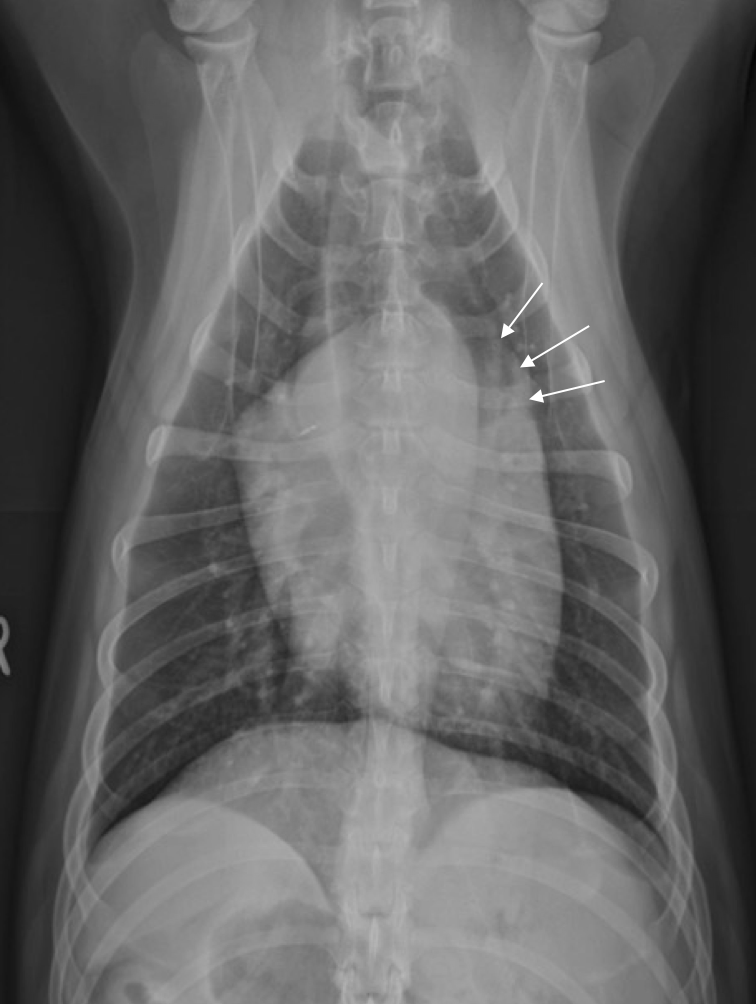

What is shown in this image?

left atrial enlargement (humpback appearance)